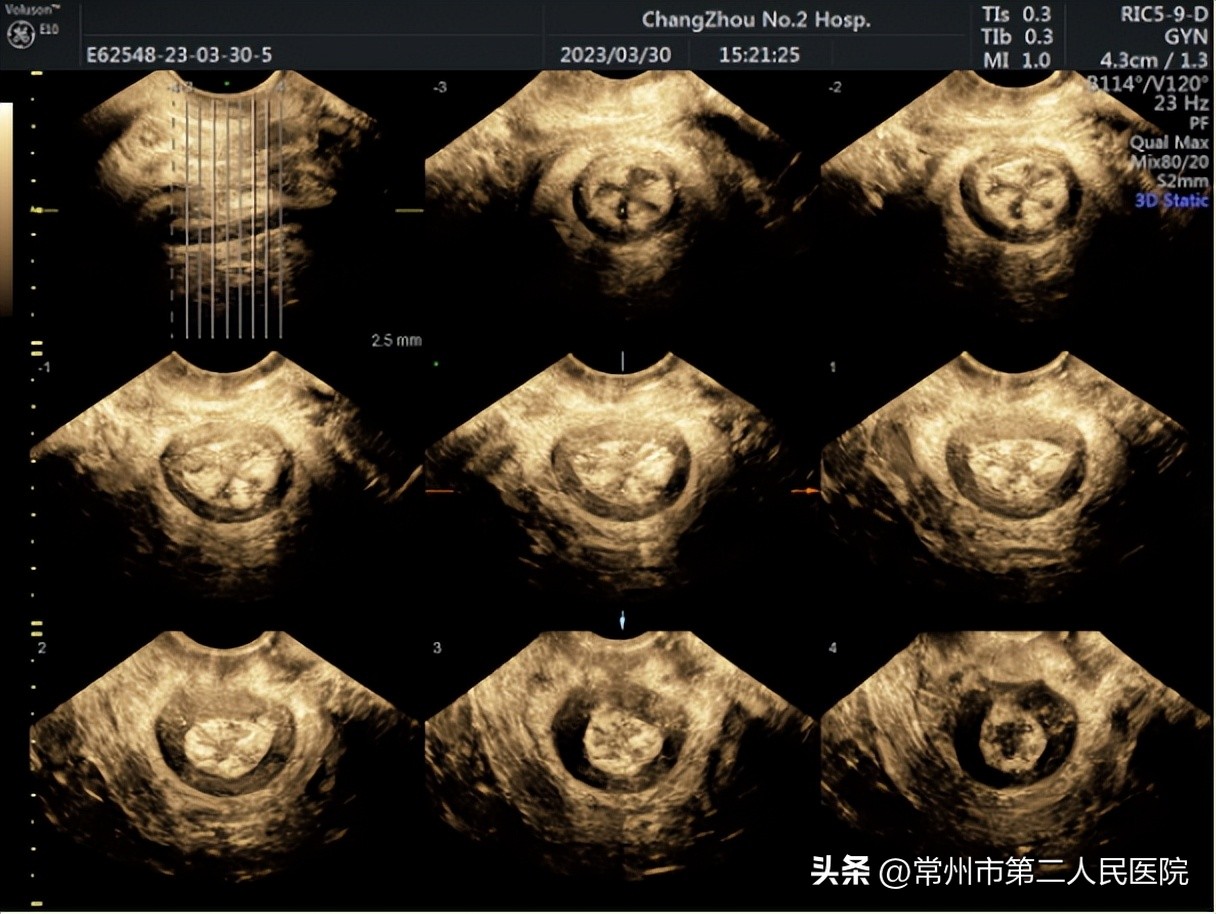

盆底功能障碍性疾病的影像学检查方法有X线、CT,MRI,超声(3D/4D),盆底超声以其无创、实时动态、准确、无辐射和廉价等优点成为盆底功能障碍首选的影像学检查。其应用超声探头经会阴及阴道多切面、多角度显示盆底解剖,评估盆底结构形态,动态观察盆底肌肉的连续性及收缩能力,以及盆腔内脏器的位置及移动情况,实时了解盆底功能。